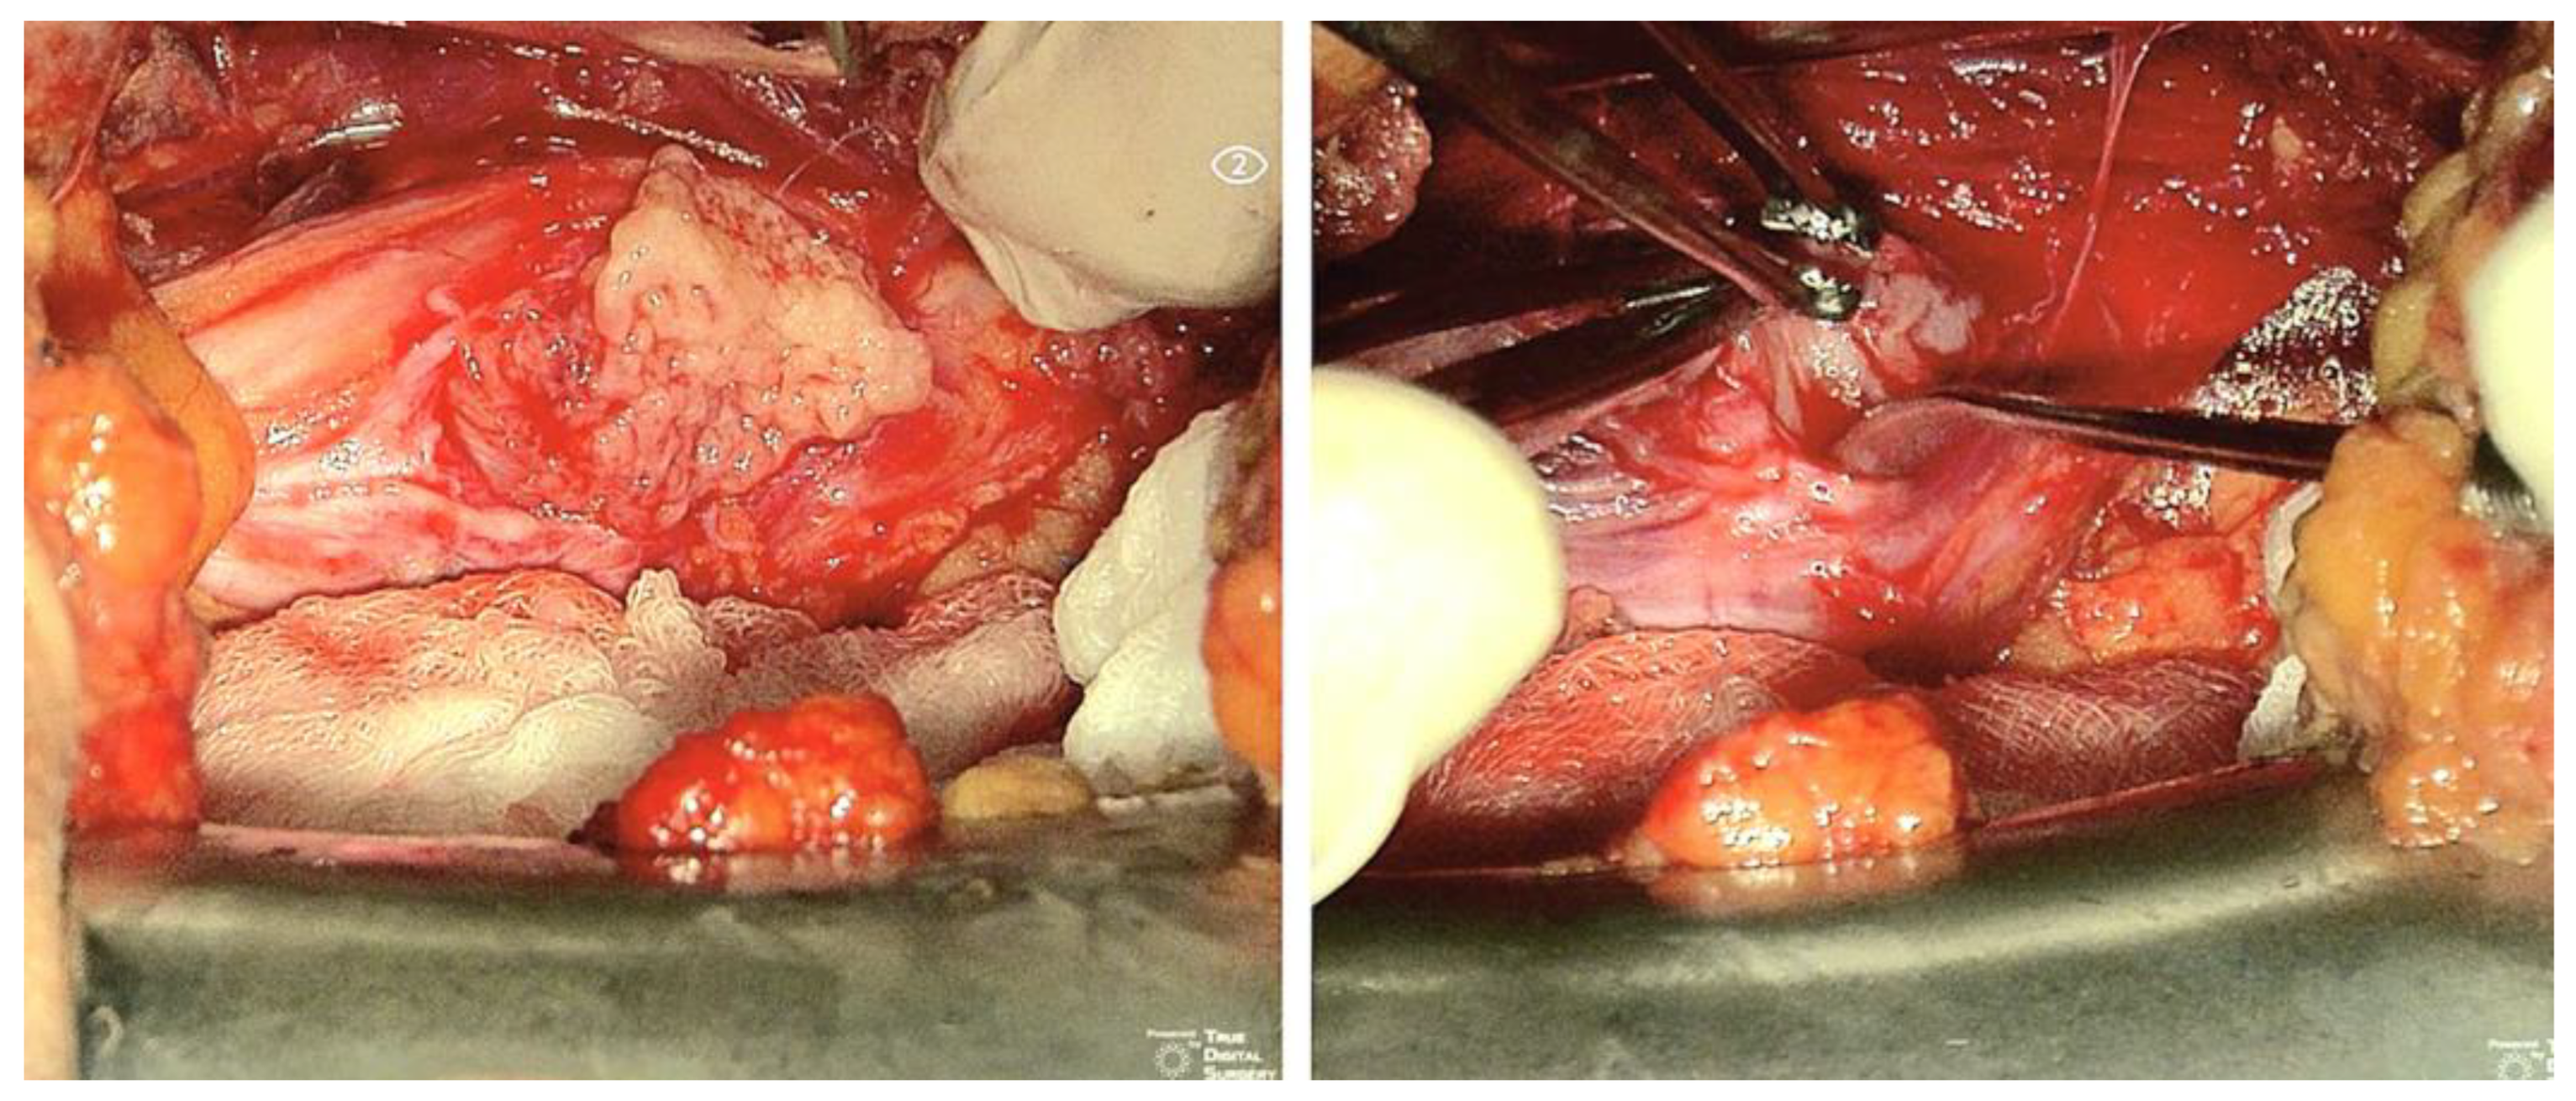

| Patient 5 | 36, F | Sacral plexus (S1-S2), pelvic presacral | S | 130 | Left sciatic hypoestesia | Lower midline laparotomy; retroperitoneal | 480 | 3000 mL; yes | 30 | Ambulating on P.O. day 1; no new deficits; paresthesias on sciatic territory (improving) | Yes; no | Yes (open) |

| Patient 6 | 56, F | Left sciatic nerve, pelvis lateral to sacrum | S | 50 | Left sciatic pain | Pfannestiel incision; transperitoneal | 420 | 500 mL; no | 24 | Ambulating on P.O. day 1; no new deficits; pain remission; paresthesias on sciatic territory (improving) | Yes; no | Yes (open) |